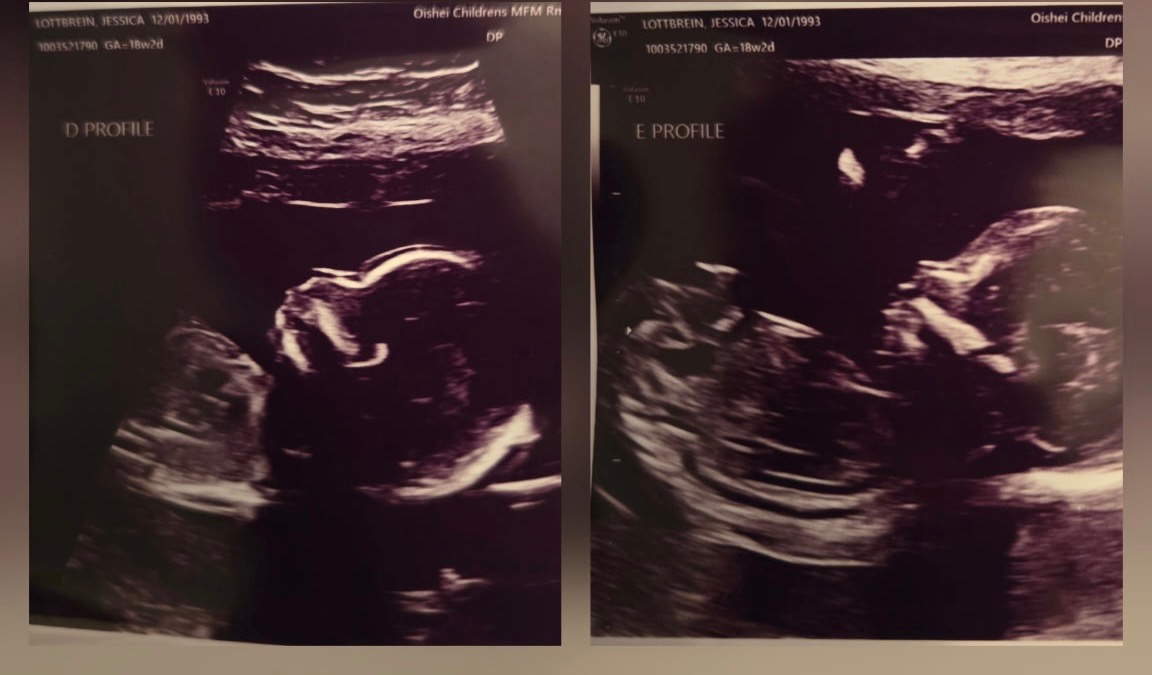

Jess is an amazing mother to her two young daughters, Hannah and Brooke, and a dedicated wife to the love of her life, John. They recently decided to expand their family and went through some fertility treatments. It was not IVF. She spontaneously released five eggs and all five were fertilized. Once again, this was not an intentional thing, nor is it something that could’ve been predicted. So now she is almost 20 weeks pregnant with quintuplets! For those of you who don’t know, that is five babies tucked safely away in her belly. The babies are thriving; they’re growing at appropriate rates, and as of right now, there’s no sign of major complications.